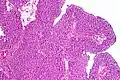

Histopathology of transitional carcinoma of the urinary bladder. Transurethral biopsy. Hematoxylin and eosin stain.

Transitional refers to the histological subtype of the cancerous cells as seen under a microscope.

The 1973 WHO grading system for transitional cell carcinomas (papilloma, G1, G2 or G3) is most commonly used despite being superseded by the 2004 WHO[14] grading for papillary types (papillary neoplasm of low malignant potential [PNLMP], low grade, and high grade papillary carcinoma). High-grade carcinoma typically displays more pleomorphism, multiple mitoses, euchromatin and relatively prominent nucleoli, and uneven distribution of nuclei.